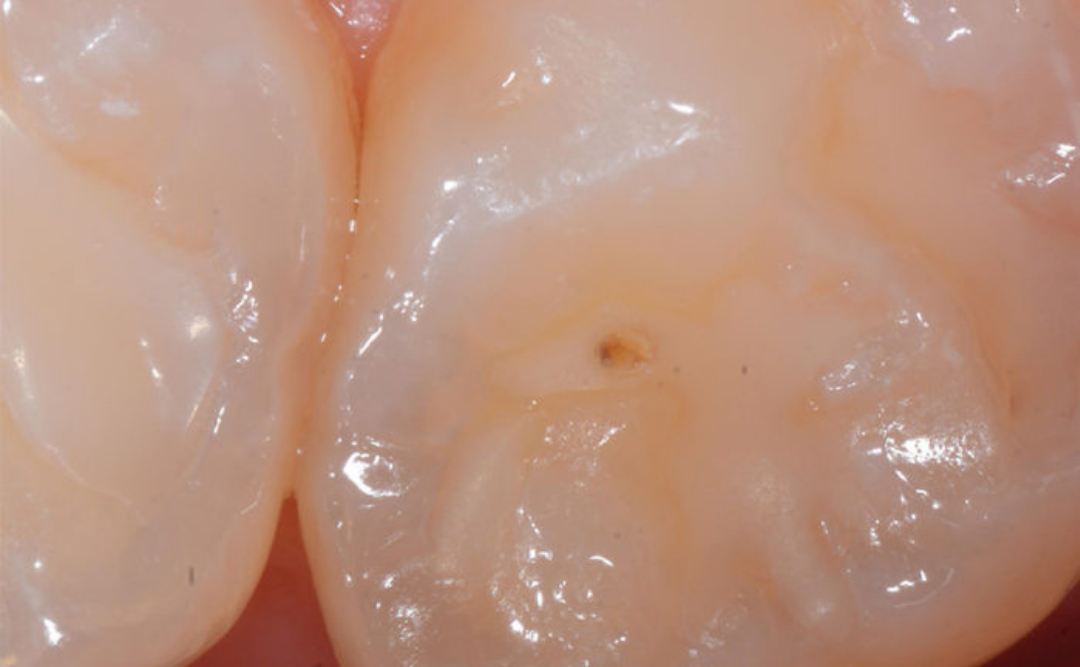

2. Durch Blasen verursachte Flecken auf der Restauration

Wenn eine Blase eine Vertiefung auf der Oberfläche eines Komposits hinterlässt, können Schönheitsfehler mit peinlichen Verfärbungen entstehen.

Eine kleine Blase im Komposit weist eine erhebliche Verfärbung auf, über die sich der Patient beschwert hat und die der Grund dafür war, dass er den Zahnarzt gewechselt hat.

Diese Blase in einer Fissurenversiegelung (Kavität der Klasse I) ist ein allzu häufiger Anblick).